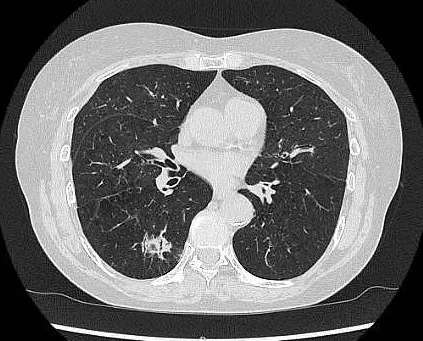

胸部単純CT検査画像 胸部単純CT検査画像

胸部単純CT検査画像(右肺がん)